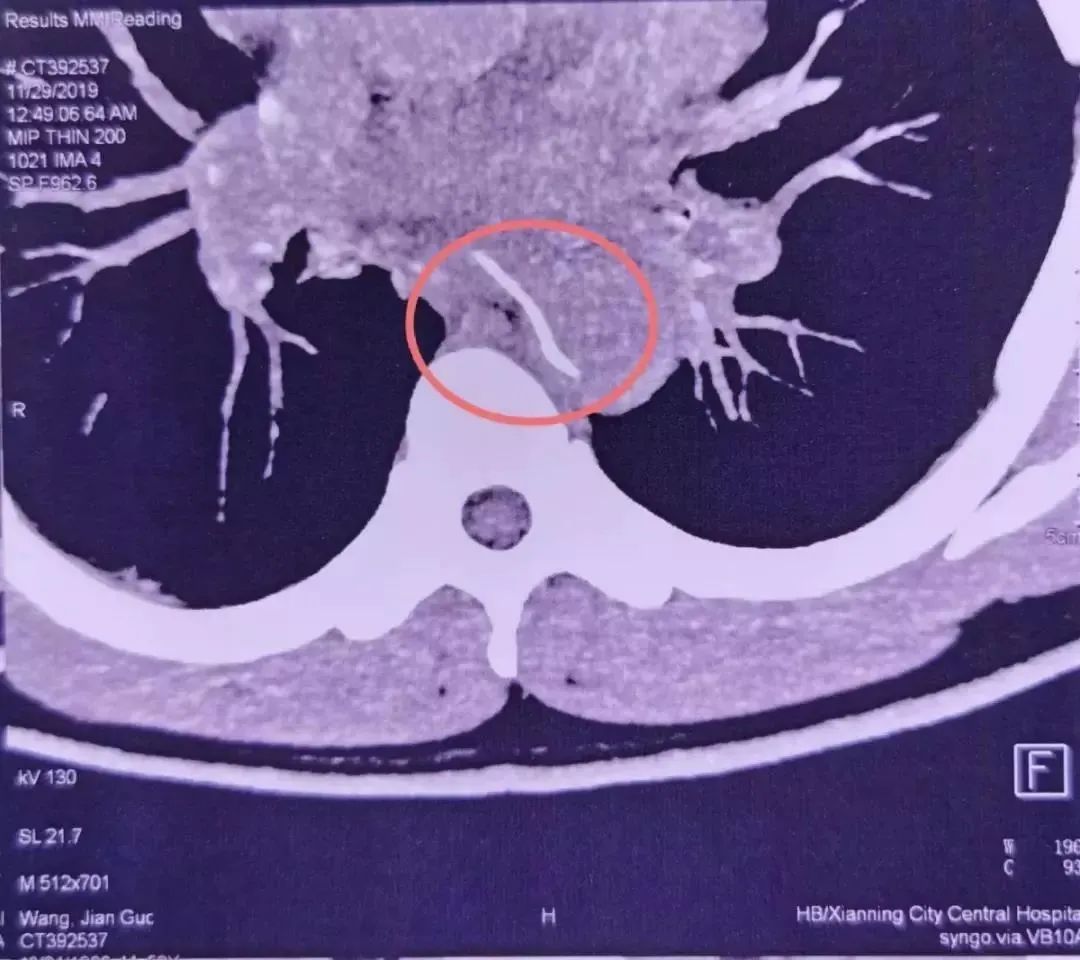

28 号这天,他突然感觉到剧烈胸痛,于是赶忙到咸宁当地的医院检查。医生很快安排了 CTA(CT 血管造影)。结果发现,一根鱼刺样的异物卡在了老林的食道内,并且已经刺穿了食道壁,扎进了胸主动脉。

第二天一大早,重症医学科的魏捷听值班医生报告了这个病例。她看到检查结果后,发现鱼刺像一把「弯刀」架在食道和主动脉之间,就像主动脉上突兀地长出了一根刺。